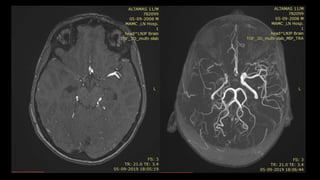

ARTERY OF PERCHERON (AOP)

INFARCTION

vascular variant

P1 PCA segment

midbrain and medial thalami

NORMA

L

VARIAN

T

Altered mental status

NCCT scans in early acute AOP occlusions are usually normal.

T2/ FLAIR images shows round or ovoid hyperintensities in

the medial thalami, just lateral to 3rd ventricle and midbrain.

• #156 This image shows a single dominant perforating artery fromP1 segment as compared to normal in which multiple small perforating branches supply the thamus and midbrain

• #158 This is a c/o AOP INFARCTION . Axial DWI images shows diffusion restriction in bilateral paramedian thalamic and midbrain region – consistent with acute infarct.